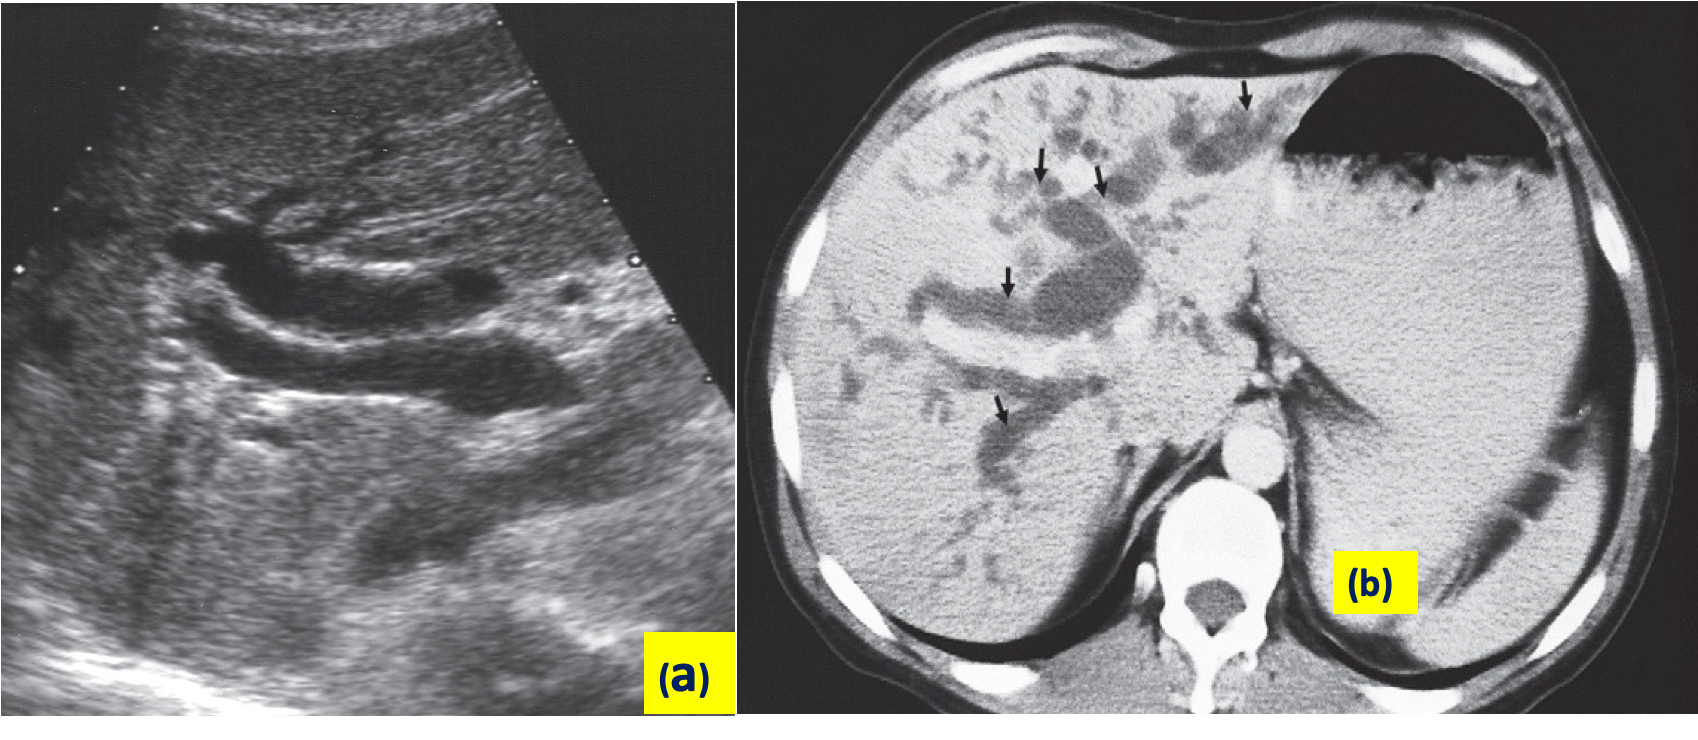

a) Ultrasound: obstructive jaundice is diagnosed by biliary dilatation, especially the intrahepatic bile ducts and it can follow down the cause of biliary obstruction. ultrasound can show gallstone, common bile duct stone, space occupying lesion in the liver, liver metastases, ascites. gallstone can appear as hyper-echoic shadow with classical âacoustic shadowingâ in ultrasound.

Dilatation of the intra- and extrahepatic biliary system can be identified at ultrasound, CT and MRI. #Z ***Ultrasound is usually the first test to be performed. ***

Dilated intrahepatic biliary ducts are seen at Ultrasound as serpentine structures paralleling the portal veins, a finding known as the âdouble channel signâ. Z

The common bile duct lies just in front of the portal vein and is dilated when more than 7 mm in diameter.

Dilated biliary ducts. - obstruction of biliary

(a) Longitudinal ultrasound scan showing a dilated common bile duct (CBD) measuring 11 mm in diameter lying in front of the portal vein (PV). Normally the duct is much smaller than the accompanying vein. A dilated intrahepatic duct is noted.

(b) CT scan showing dilated intrahepatic ducts (arrows) in the liver.